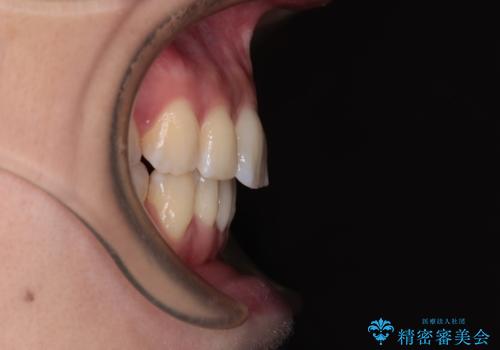

- 口元の閉じにくさを気にして来院された患者様です。

上下ともに歯列が前方に突出していたため、上下左右の第一小臼歯4本を抜去し、ワイヤー装置による矯正治療を行うこととしました。

舌の突出癖がなかなか改善されず、上下前歯の接触がやや甘い状態での仕上がりとなりました。

接触が甘い場合、上顎前歯の叢生が後戻りを起こしやすくなるため、治療終了後の保定期間でも舌のトレーニングを継続するように指示しています。